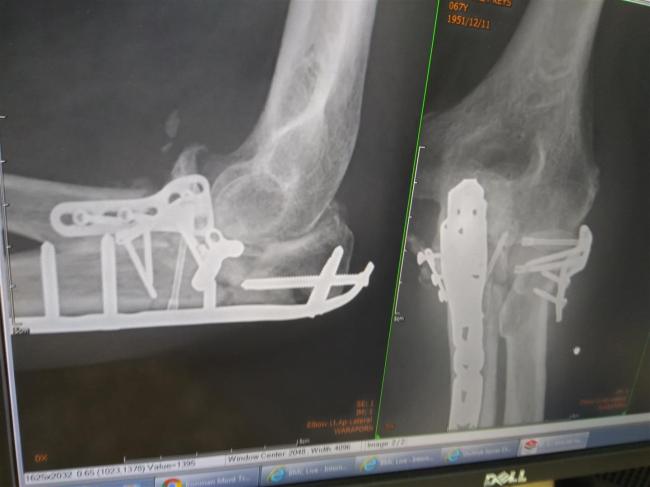

Not a pretty sight, is it.

I came round at about 21.15, after six and a half hours in surgery. I was in lots of pain and discomfort and spent the night drifting in and out of sleep, constantly asking for pain relief. By the morning the pain was worse! A doctor came round and adjusted the plaster splint, bringing immediate relief to my swollen arm and hand. They also set up a self managed morphine supply. That was nice! The surgeon came to talk me through what he’d done and he showed me the x-ray so I could see all the metalwork inside. He checked that I could move my hand and fingers satisfactorily, meaning that there was no nerve damage. I’d be stuck with the plaster splint for four weeks, then I’d get a light weight plastic and metal splint, enabling me to start moving the elbow. It would be around four to five months before I’d be able to ride my bike. He explained how some of the cartilage had been carried away by the broken bone and that because it had no blood supply, would not be able to repair itself. The operation wounds had been stapled together and he cleaned them up then put the splint back on. The x-rays will give you an idea of how bad the damage to the bones is.

Some very delicate steelwork sits inside, holding my bones together.